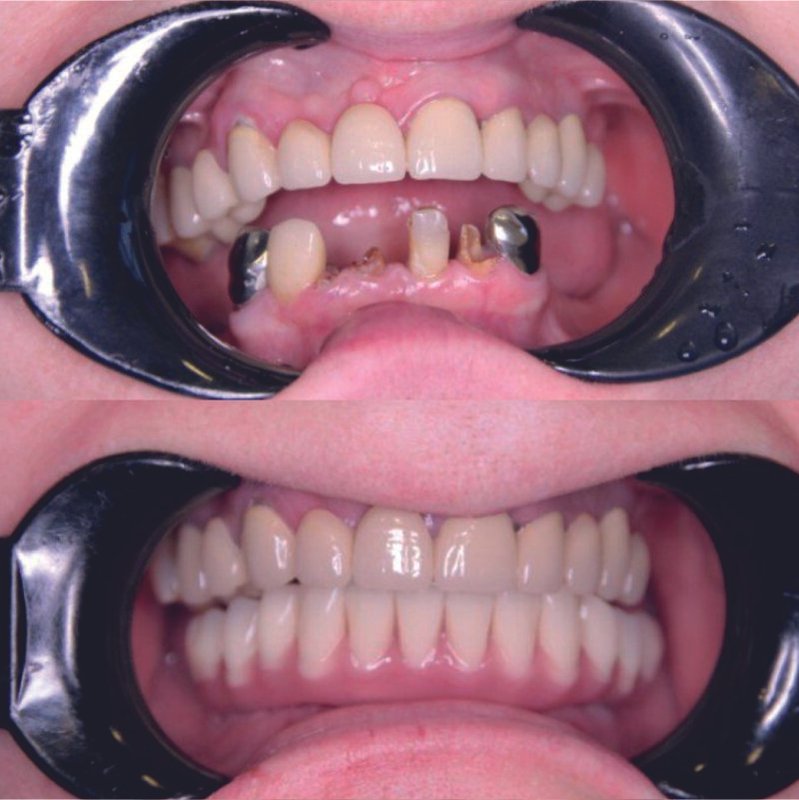

Фотогалерея